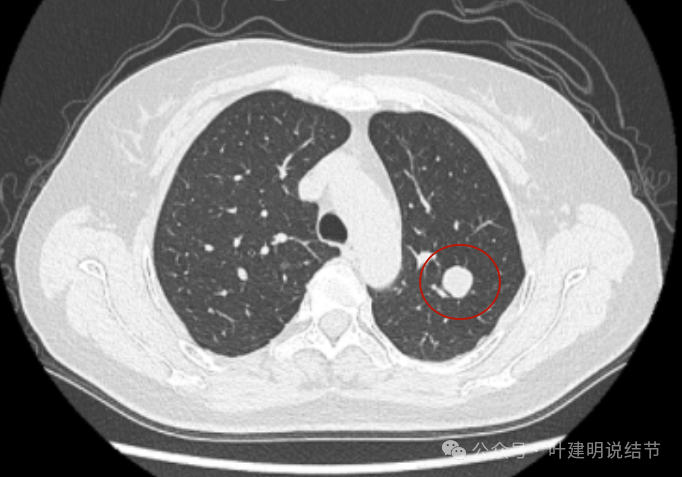

2020年5月,病灶仍是边缘非常光滑,局部表面似有凹陷。

2021年9月,病灶相仿,但与邻近血管的距离似乎较最初的更靠近一点。